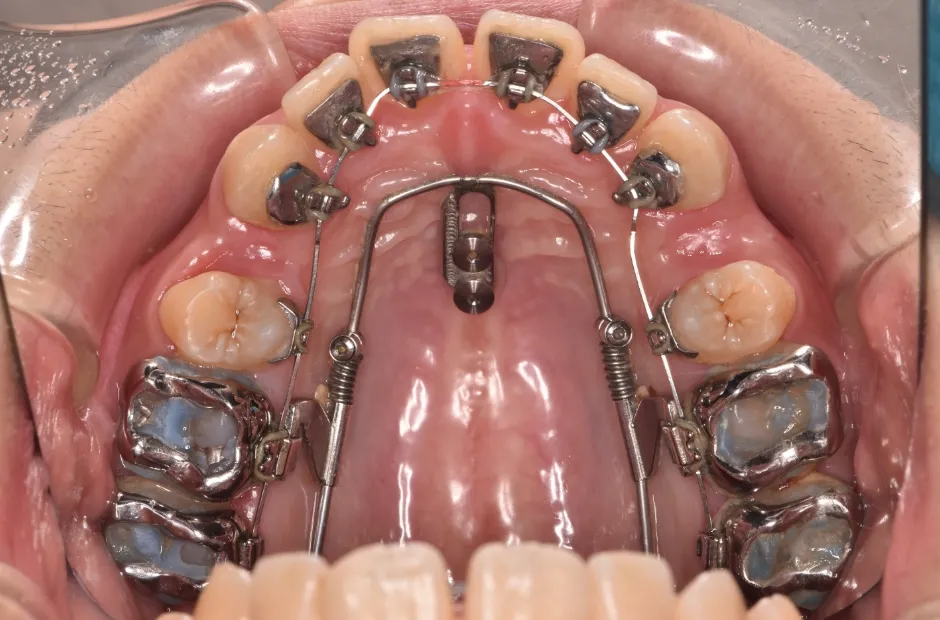

開咬

| 診断名・主訴 | 開咬 |

|---|---|

| 年齢・性別 | 18歳・男性 |

| 治療期間・回数 | 1年 12回 |

| 治療に用いた主な装置 | ロール付きリンガルアーチ |

| 抜歯部位 | なし |

| 治療費 | 70万円(税抜) |

| リスク・副作用 | 装置による違和感・疼痛・歯肉退縮・歯根吸収・虫歯のリスクなど |

治療中